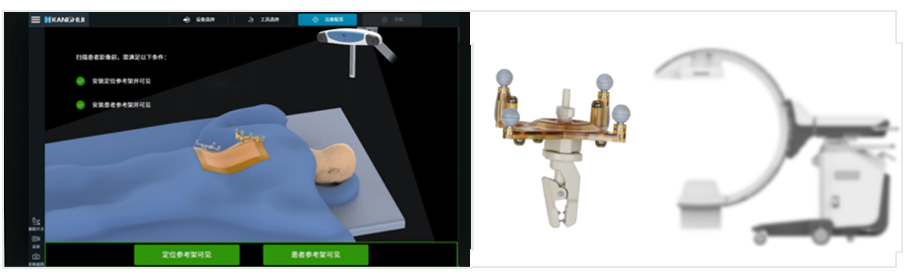

全型號三維影像自動配準

無縫銜接智能手術生態提高團隊效率

10秒內自動配準

配準算法精度可達0.19mm